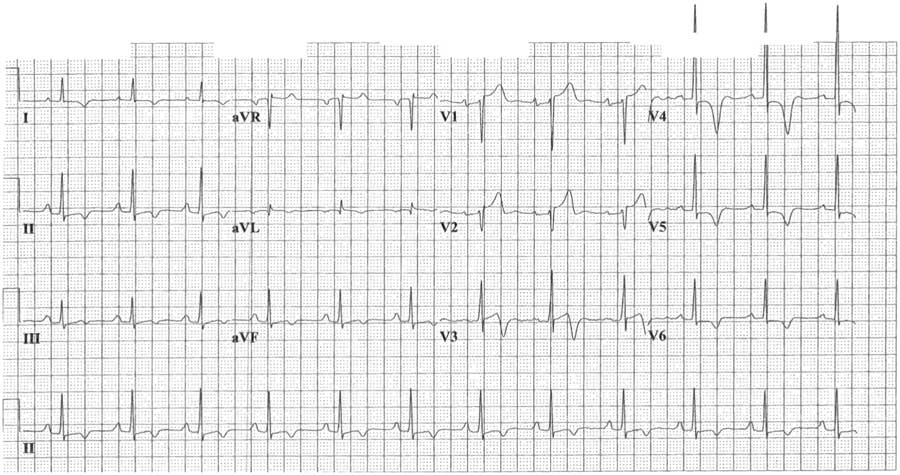

The patient was treated for an acute ST-elevation myocardial infarction (STEMI) in the ED and was later admitted to the coronary care unit (CCU) after the initial treatment. He was initiated on aspirin, clopidogrel, intravenous heparin infusion, and atorvastatin. As the patient presented to a non–percutaneous coronary intervention (PCI) capable hospital, the anticipated first medical contact to device time was >120 minutes; tenecteplase 50 mg was administered intravenously 60 minutes into his presentation. The patient was free of chest discomfort 90 minutes into admission. During admission, serial ECGs showed no resolution of the ST-segment elevation and persistent T-wave inversion (Figure 1). High-sensitivity cardiac troponin T was within normal limits, and both troponin and creatine kinase remained stable over several days. A coronary angiogram performed 13 hours into his presentation revealed normal coronary arteries without evidence of obstructive coronary disease with a left ventriculography demonstrating obliteration of the apical cavity at end-systole (Figure 2). Transthoracic echocardiography revealed a progressive increase in LV wall thickness toward the apex without evidence of LV systolic dysfunction or outflow tract obstruction (Figure 3). However, apical views were suboptimal, and no spade-like appearance of the apex was observed. On admission day three, the patient was discharged home on metoprolol.

Figure 1 Index 12-lead electrocardiogram showing concave ST-segment elevation in leads V1-V2, ST-segment depression in leads V4-V6, and diffuse T wave inversion. In lead V4, the T wave was symmetrically inverted to a depth of 10 mm and the R wave was prominent, measuring at least 30 mm.